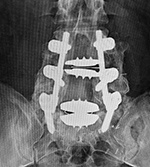

| Metal-on-polyethylene total disk replacement at L4-5 |

| 46 year-old woman with degenerative disk disease. There is also a ligamentous fixation screw at L4. |